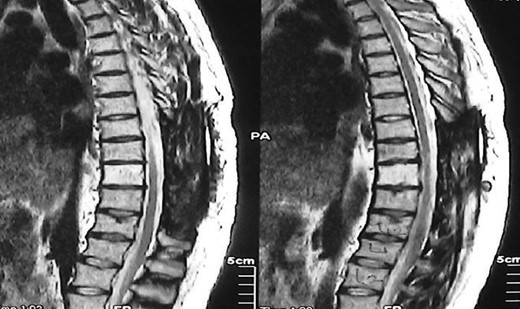

A 30-year-old male patient was admitted to our clinic with back pain. Pain was provoked by movements. The severity of pain was associated with the inability to perform the activities of daily living. The patient did not have any lymphoma-related B-type symptoms, including body weight loss, fever and sweat at night. He did not have a past and family history. There was no neurological deficit. Routine laboratory test results were normal. A magnetic resonance imaging (MRI) scan of the thoracic spine demonstrated an epidural tumor at the T9–11 level (Figs 1–3). The patient underwent spinal cord decompression via total laminectomy of T9–11 levels. Subtotal resection of the tumor was performed. Histological examination revealed the polymorphous cellular infiltration by histiocytes, large mononuclear cells and lacunar Reed–Sternberg cells with folded multi-lobed nuclei and small nucleoli (Fig. 4). Immunohistochemical staining was positive for CD15 and CD30 and negative for CD3, CD20, CD79a or CD45Ro. These features were most frequently observed in the mixed cellularity type of Hodgkin's lymphoma. Histological examination of the vertrebral body revealed no abnormality. The results of all other examinations (F-18 fluorodeoxyglucose positron emission tomography (F-18 FDG PET/CT), bone marrow biopsy and computed tomography (CT) of the chest, abdomen and pelvis) were negative for an occult disease. The patient was referred to the hematology department to undergo staged treatment. Six courses of chemotheraphy containing ABVD regimen (adriamycin, bleomycin, vinblastine and dacarbazine) were given to the patient. Postoperative MRI scan did not reveal any evidence of Hodgkin's disease (Fig. 5), F-18 FDG PET/CT, CT of the chest, abdomen and pelvis were obtained in 24 months and did not reveal any evidence of Hodgkin's disease.

Postoperative MRI scan did not reveal any evidence of Hodgkin's disease.

Moridaira et al. [4] reported a case of Hodgkin's disease at T8–10 epidural space. Rao et al. [6] published a case with primary spinal epidural Hodgkin's lymphoma. Our case is apparently the seventh case to be diagnosed with Hodgkin's disease who presented with spinal cord compression due to epidural space without lymphoma elsewhere. The abnormal MRI marrow signal of the T9 and T10 vertebral bodies can be seen in Fig. 5. Maybe the tumor in fact originated within the abnormal T9 or T10 bone marrow and spread to the epidural space via the epidural venous plexus. But histological examination of the vertebral body revealed no abnormality.

Surgery is the first therapeutic approach in malignancies compressing the spinal cord. Because Hodgkin's lymphoma is a very chemosensitive and radiosensitive tumor, the indications for surgery were reduced and limited to laminectomy or even biopsy only, leaving the major role to chemotheraphy and radiotheraphy. The combination of chemotheraphy and involved-field radiotheraphy is the most common treatment strategy; two to four cycles of ABVD are considered as the international gold standard for early-stage Hodgkin's lymphoma in combination with 20–30 Gy of involved-field radiotheraphy [7, 8]. We chose the first therapeutic approach for this patient who underwent gross total resection of the tumor, because the tumor type was unknown at the time of initial presentation. Also, there was severe thoracal spinal cord compression on MRI of our case. Then, the patient was given six courses of chemotheraphy through ABVD regimen.